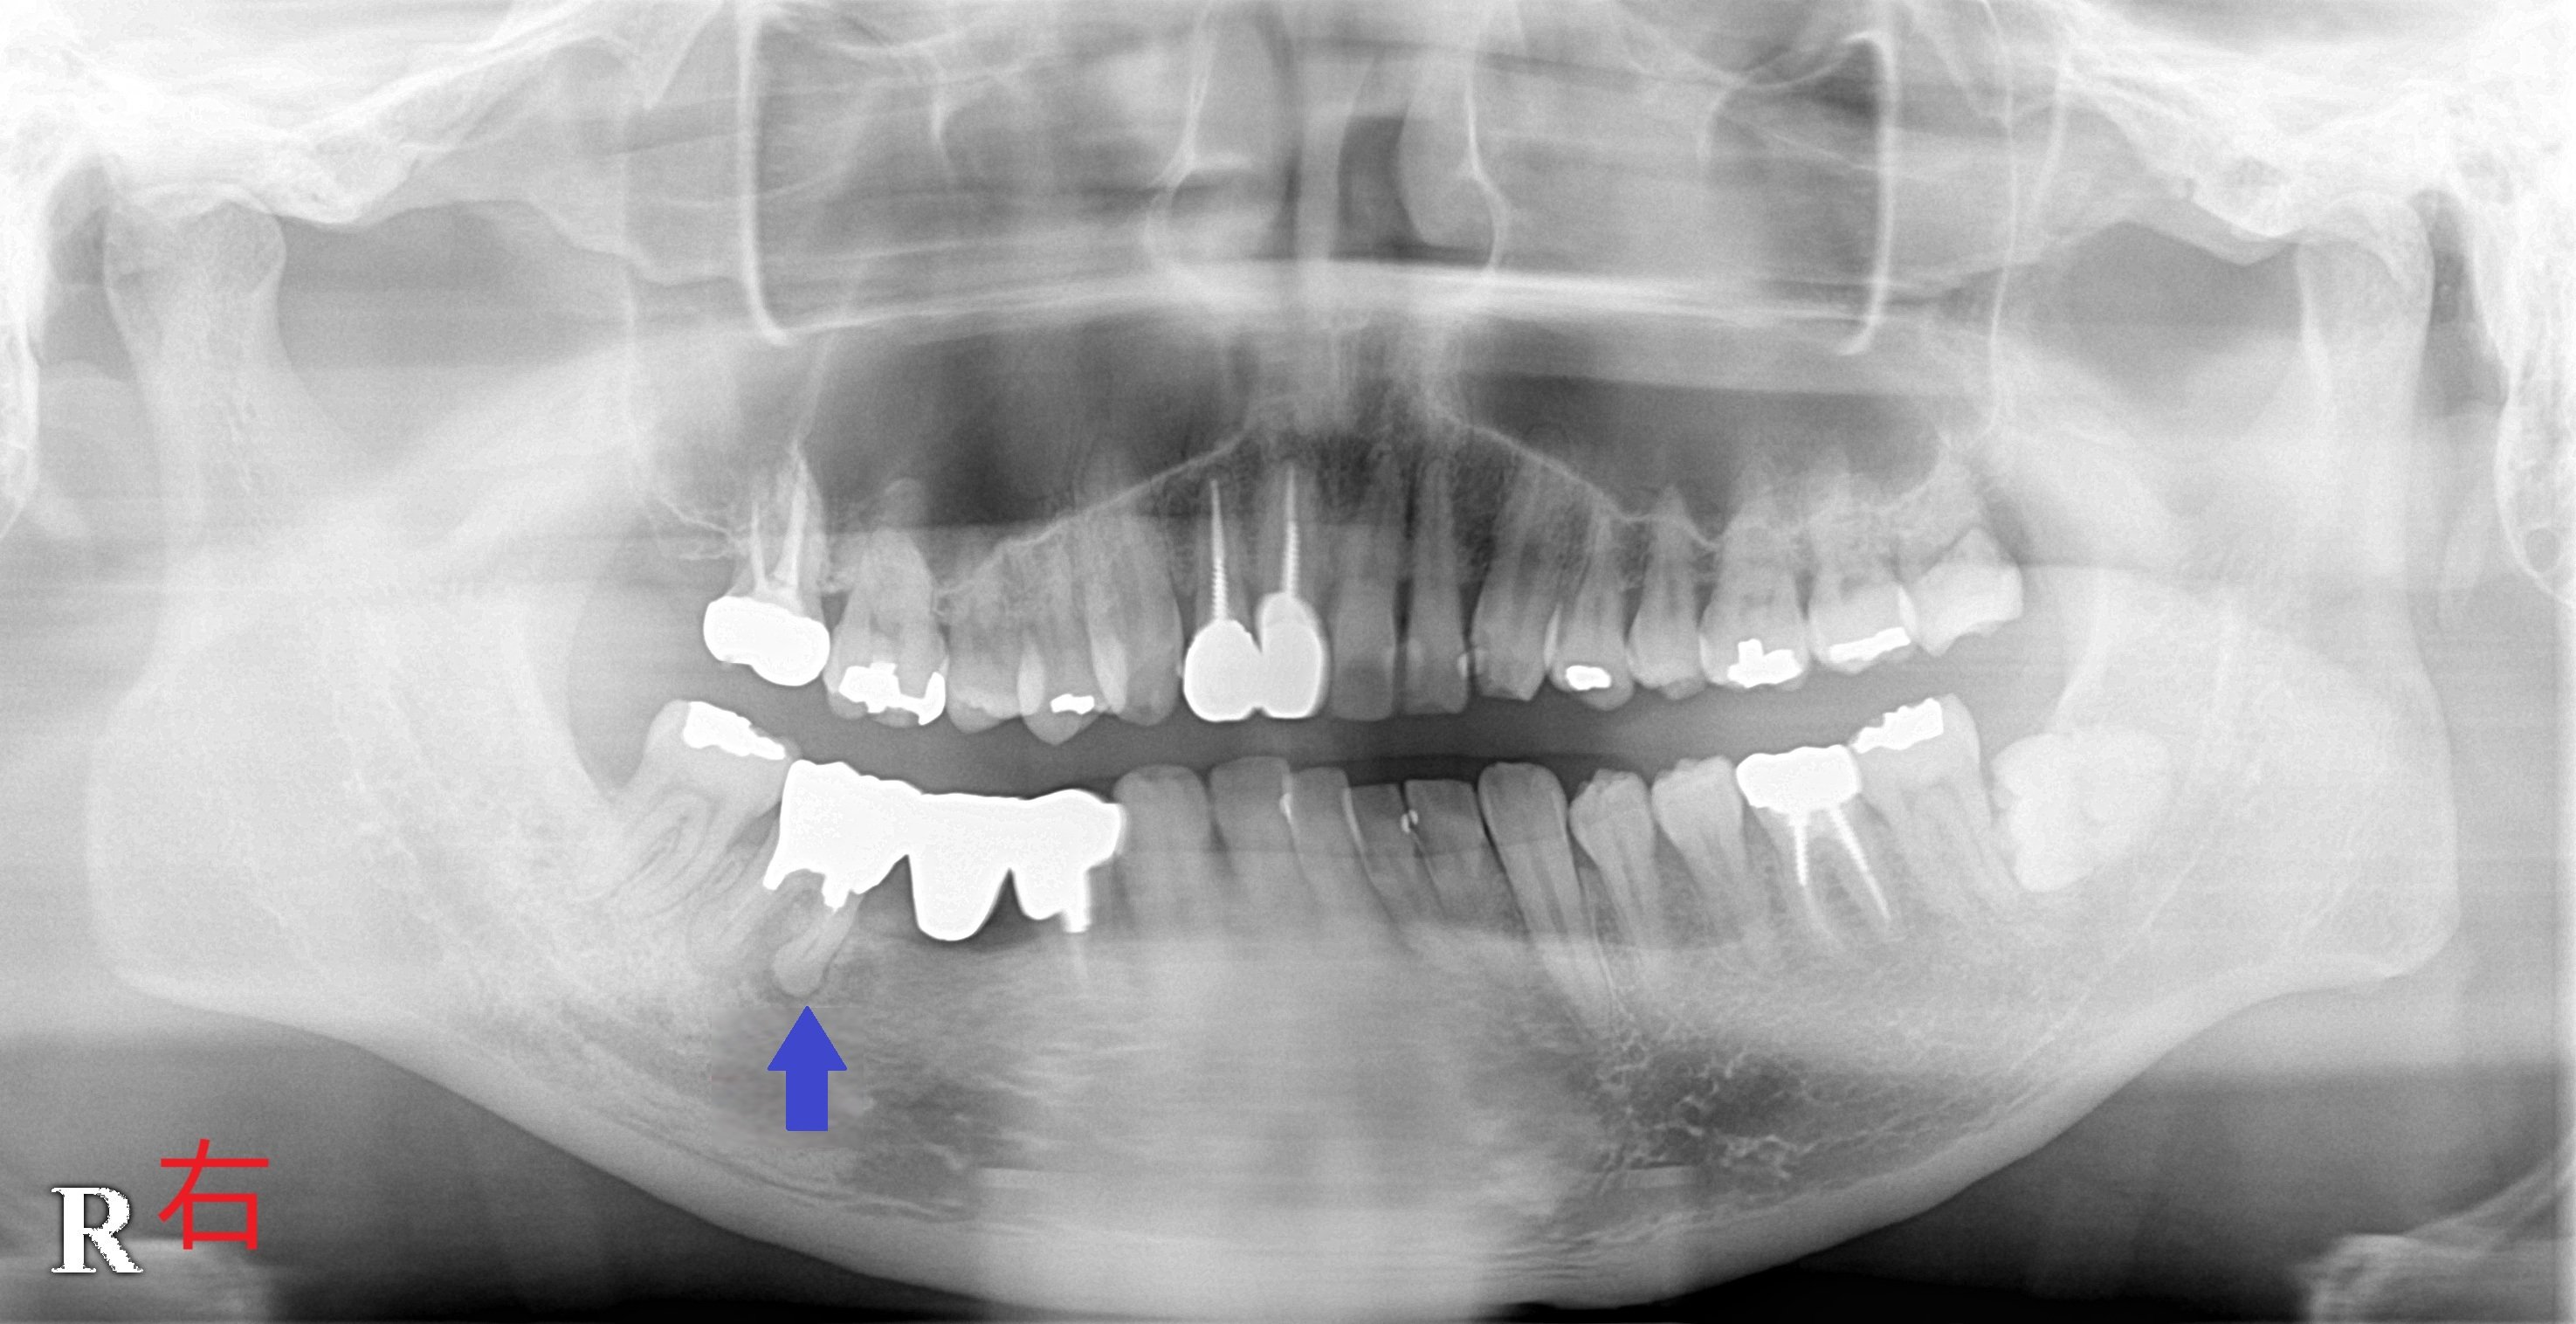

青色矢印の歯が破折し、歯根の周囲の骨が吸収されている様子が確認されます。

神経を除去した歯は、神経が残っている歯と比較して強度が著しく低下するため、歯根破折のリスクが高くなります。実際、矢印の前方にある歯も神経を除去しており、同様のリスクが懸念されます。